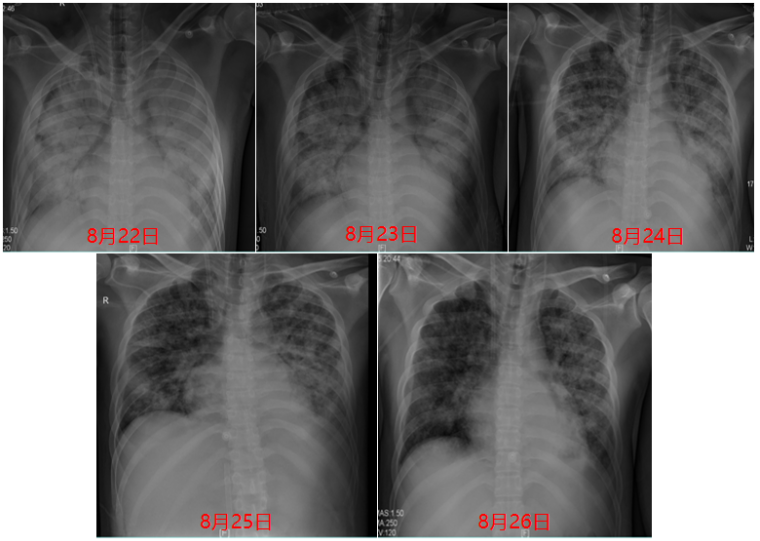

经过5天左右的治疗,患者病情较入院时明显改善(图13),肺部超声提示肺水较前明显减少。

图片

图13  8月22日-8月26日胸片变化

撤离ECMO后复查胸部及颅脑CT提示:肺部病变较前明显吸收,心脏超声提示心功能明显改善。ECMO撤机后的呼吸机参数:FiO2 40%,压力支持16 cmH2O,监测潮气量480 ml左右,顺应性30 ml/cmH2O左右。